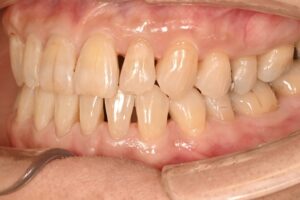

前歯の重なりが気になるというお悩みをお持ちの患者さんです。

ご年齢は60代の方です。

横から見ると、下の前歯が少し凹んでいます。

その辺りの歯の重なりを治したいですね。

上下の歯ならびを別の角度から見ています。

下の歯がガタガタしているのがわかります。